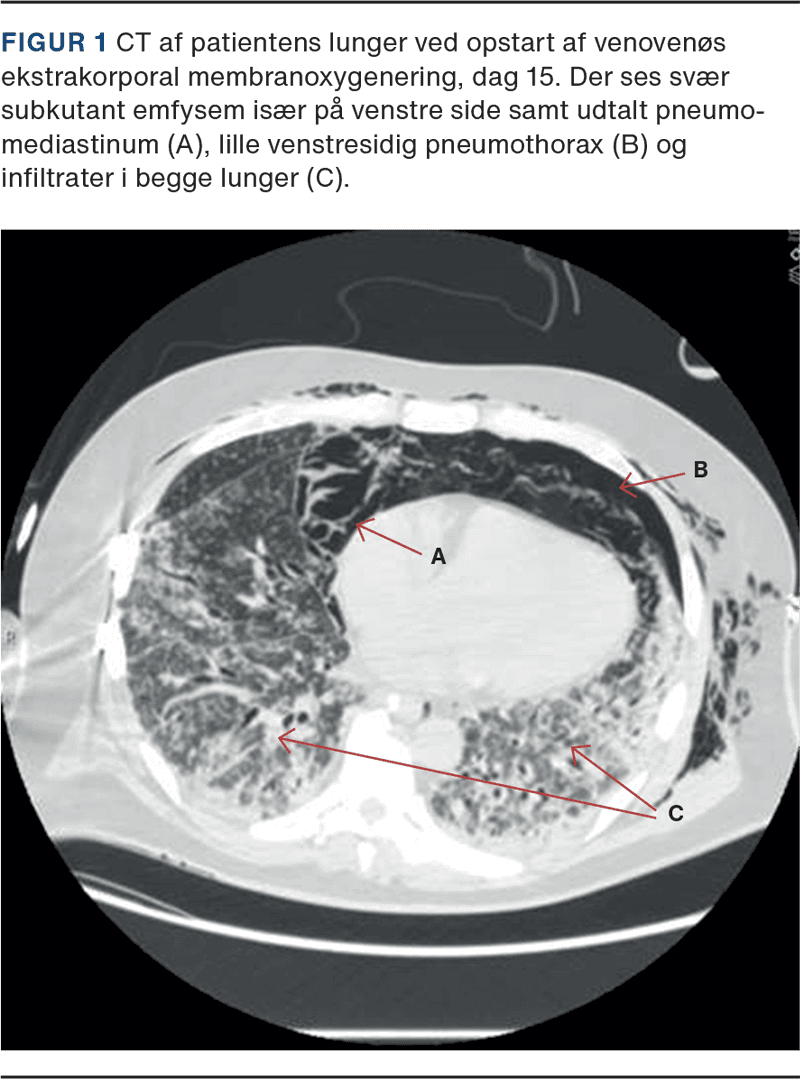

En 49-årig mand, ellers sund og rask, var involveret i et højenergitraume og pådrog sig bl.a. en traumatisk næramputation af højre overekstremitet (OE) med store bløddelslæsioner og fraktur af humerusskaftet. Han gennemgik gentagne operationer af højre OE med debridement, ekstern fiksation, vacuum-assisted closure (VAC)-behandling og intern fiksation. Han blev herefter henvist til højt specialiseret afdeling grundet bløddelsnedbrud over frakturstedet. Her blev der foretaget fjernelse af marvsøm, forkortning af humerus og skinneosteosyntese samt direkte lukning af bløddelsdefekten. Grundet frakturrelateret infektion med Staphylococcus epidermidis i vævsprøver opstartedes behandling med peroral clindamycin 600 mg × 3. Postoperativt opstod der fornyet bløddelsnedbrud. Der blev foretaget sårrevision og opstartet VAC-behandling. Vævsprøver var positive i 5/5 Kammesæt for Escherichia coli og Stenotrophomonas maltophilia. Der blev opstartet peroral ciprofloxacin 500 mg × 2 og sulfamethoxazol med trimethoprim 1600/320 mg × 4 – herfra defineret som dag 0. Dag ni blev der, på mistanke om pneumoni, startet behandling med amoxicillin med clavulansyre 500/125 mg × 3. Dag 11 blev han indlagt på lokalsygehus grundet stigende infektionstal, feber og lav iltsaturation. Dag 14 blev han intuberet grundet et pågående højt iltkrav (FiO2 100%), og dag 15 overflyttet til behandling med VV-ECMO (CT fra dag 15 kan ses i Figur 1). Til trods for intens fokusjagt inkl. gentagne dyrkninger af blod og trakealsekret (også fra bronkoalveolær lavage) blev en infektiøs årsag til hans respirationsinsufficiens aldrig påvist. Lungeemboli blev udelukket af flere omgange. På mistanke om sulfamethoxazol med trimethoprim-induceret pneumonitis blev dette seponeret efter i alt 17 dages behandling, og CRP faldt.